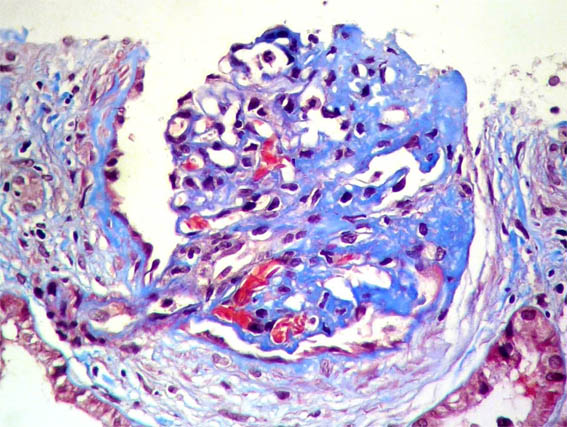

Figure 9.

Methenamine-silver stain,

X400.